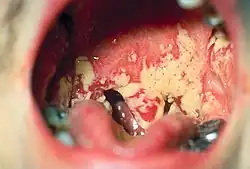

Unter einer Stomatitis (von griechisch Stoma = Mund und -itis, veraltet auch Mundkatarrh) versteht man eine Entzündung der Mundschleimhaut. Sie stellt eine eigene Krankheit dar, kann aber auch ein Begleitsymptom einer anderen Krankheit oder Nebenwirkung einer Therapie sein.

Die Mundschleimhaut ist gerötet und entzündlich verändert – die klassischen Entzündungszeichen sind sichtbar. Weitere Symptome sind Mundgeruch, Appetitlosigkeit bis hin zur kompletten Ess- und Trinkverweigerung (bei Kleinkindern), vermehrter Speichelfluss (Hypersalivation) sowie leicht auszulösende Mundschleimhautblutung (z. B. durch eine harte Zahnbürste).